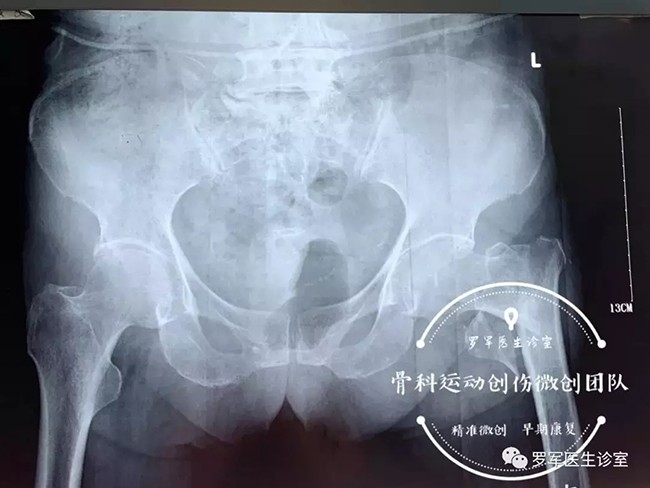

今年86歲高齡的丁奶奶就是其中的一位患者,前不久,丁奶奶走路時不幸摔倒,造成左側(cè)股骨粗隆間粉碎性骨折,被送到廣安醫(yī)院關(guān)節(jié)科救治。

經(jīng)過入院檢查發(fā)現(xiàn)丁奶奶合并有高血壓,糖尿病,動脈粥樣硬化、低蛋白血癥及嚴重的骨質(zhì)疏松,“無論采取保守治療還是手術(shù)治療,風(fēng)險都很大。但對于高齡老人的骨折,放棄手術(shù)就等于放棄生的希望。”羅軍主任介紹,髖部骨折對高齡、身患各種慢性病的老年人來說無疑是大難題,而且由于骨折后老人臥床至少需要三個月以上,由此引發(fā)的并發(fā)癥,如褥瘡,肺炎、血栓、泌尿系感染等都很容易導(dǎo)致老人死亡。因此,髖部的骨折被稱為老年人“人生的最后一次骨折”。

5月7日,羅軍主任帶領(lǐng)手術(shù)團隊按照術(shù)前的討論方案,在C臂機透視下,采用三個微創(chuàng)手術(shù)通道,施行精準(zhǔn)閉合復(fù)位、定位、固定,僅用了大約30分鐘,便成功完成微創(chuàng)內(nèi)固定手術(shù)。手術(shù)進行順利,第二天老人就可以在床邊坐起了。老奶奶非常開心,叫家人一定要送面錦旗給醫(yī)生。